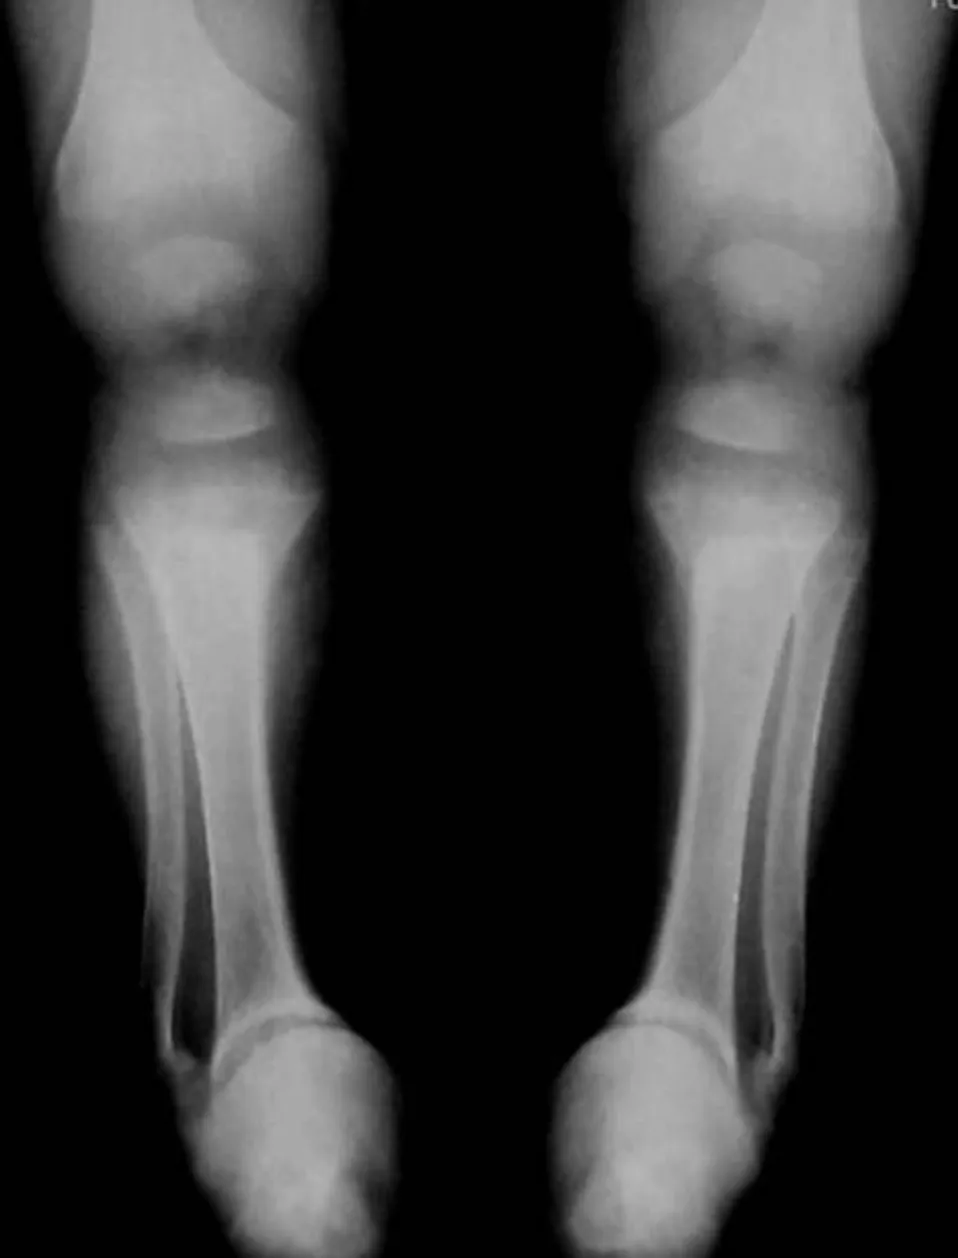

【114-1 醫學(四) 第75題】

出生 4 個月大的早產兒,因小腸壞死長期使用靜脈營養注射,因雙側踝關節變形所照的 X 光影像如圖示,下列何者為最常見的診斷?

詳解

破題關鍵

這道題的關鍵在於將早產兒、長期靜脈營養注射的病史,與 X 光影像中典型的生長板(growth plate)異常變化連結起來。

選項拆解